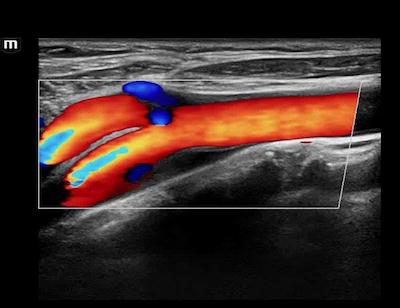

HR Flow of Common Carotid Artery and Carotid Bifurcation

HR Flow of the Main Portal Vein and hepatic branches